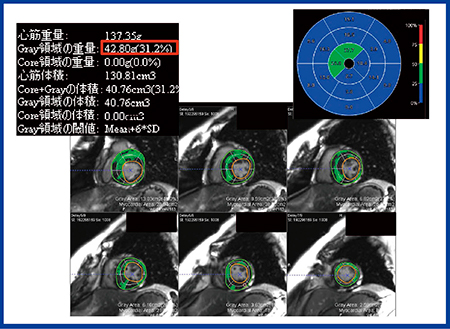

LGEは視覚的評価が基本だが,造影の強さや広がりの客観的評価,重症度や予後評価のためには定量解析が必要となる。Ziostation2の「MR遅延造影解析」では,正常心筋の信号をリファレンスとして,一定のSD以上の信号を異常心筋として抽出し,それをLGE volume(%LV mass)として計算できる。図3はHCMの症例で,6SD以上で抽出するとLGE volumeは31.2%となった。われわれの検討では,このLGE volumeによる定量化は,HCMや心サルコイドーシスなどの非虚血性心筋症の予後や治療効果予測に有用だという結果が得られた。一方で,LGEの定量解析においては,びまん性心筋疾患のように正常心筋が決めがたい場合のリファレンスの決め方が問題であり,また,SDの設定によって結果が変化することにも注意が必要である。

図3 「MR遅延造影解析」による解析